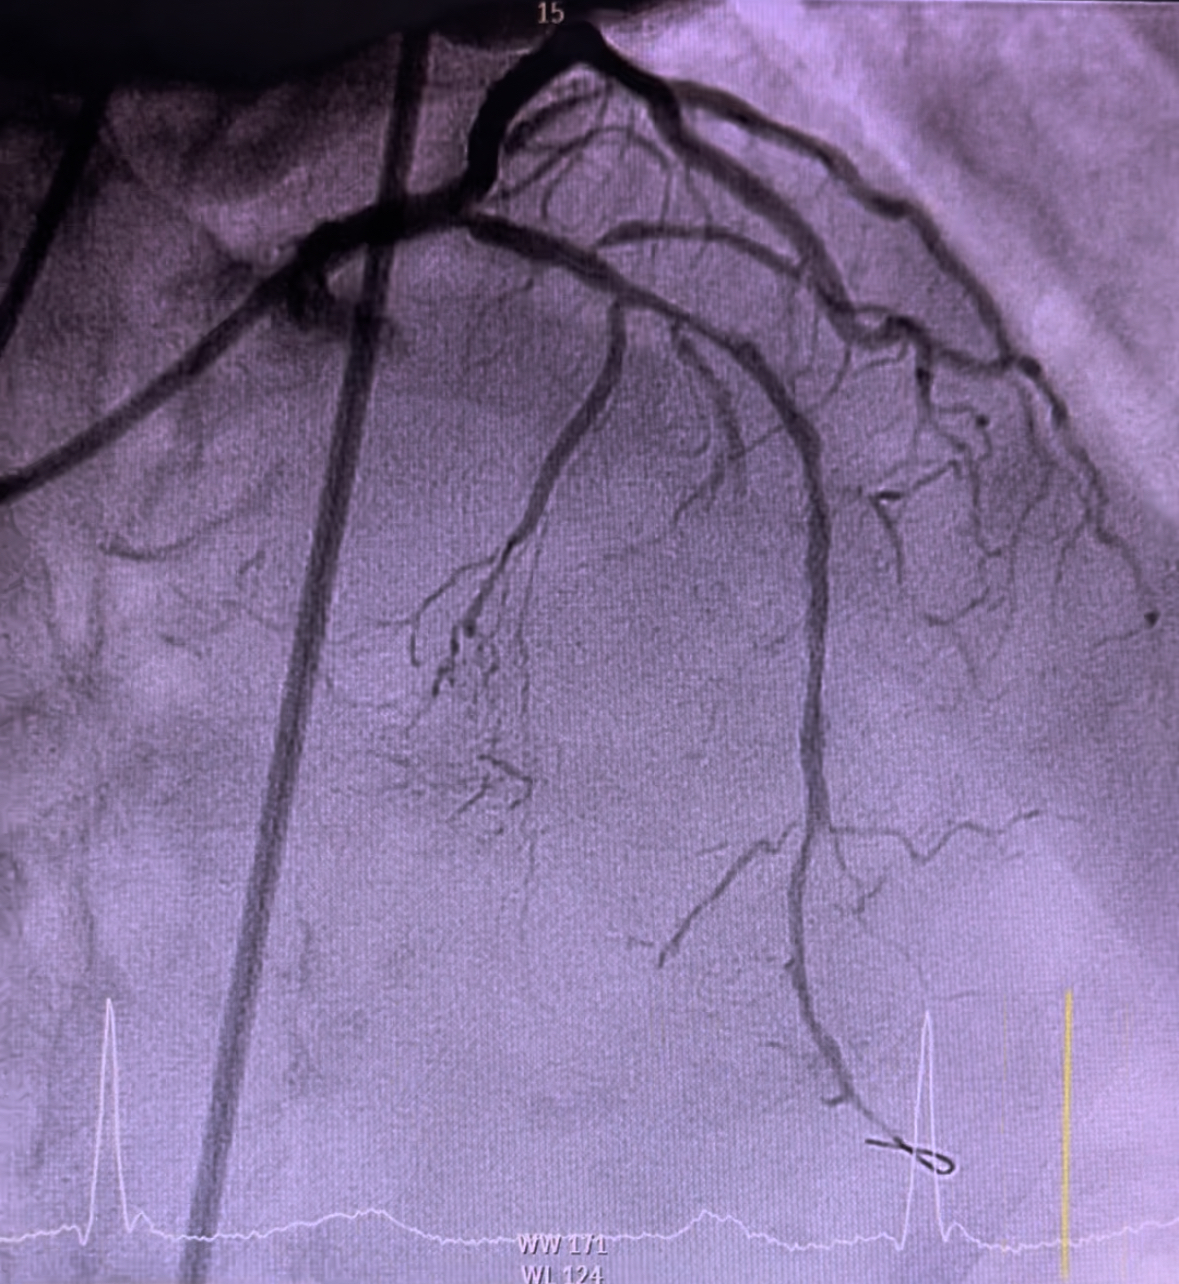

Angioplasty to left circumflex was begun by catheter engagement with XB LAD 3.5 7Fr. Wiring was done with run-through followed by lesion preparation using NC Sapphire 2.5 x 15mm inflated at 12atm. Subsequently, serial upsizing dilation was done with NC Sapphire 3.0 x 15mm inflated at 14atm. A 3.0 x 18mm stent was deployed displaying a good angiographic result. Subsequently, wiring was attempted through the LAD using Runthrough via fine cross microcatheter. Failure to pierce through the calcified stenosis has led to an escalation of guide wire to Gaia second which able to pass through successfully. Fine cross was removed using hydraulic technique with balloon inflator. Initial preparation was done by inflating NC Sapphire 1.0 x 10mm followed by 1.5 x 10mm. Thereafter, the wire was changed to Rota wire extra support via fine cross microcatheter. Rotational atherectomy was performed using 1.5mm burr, rotating at 180,000 rpm with 3 runs back and forth from proximal to mid. Further cracking was performed using intravascular lithotripsy with a 3.0mm balloon inflated at 4atm with total of 25 pulses. Further optimization was done using NC Sapphire 2.5 x 15mm and 3.0 x 15mm expanded in the mid and proximal segments respectively. Two stents sized 3.0 x 38mm and 3.5 x 38mm were respectively deployed at mid and proximal segment via guide extension. Expansion optimisation was done with a 3.5 x 15 NC Sapphire achieving TIMI 3 flow and reestablishing the flow through the side branches.

Case Summary